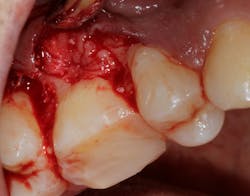

Saving compromised multirooted teeth with root amputation can often be successful, but the technique is sensitive and complex. Proper case selection is essential, and considerations include the following:

There is sufficient bone support around the remaining roots (at least 50% or more is needed) along with sufficient coronal tooth structure (figure 3).How does root amputation compare with other surgical procedures?